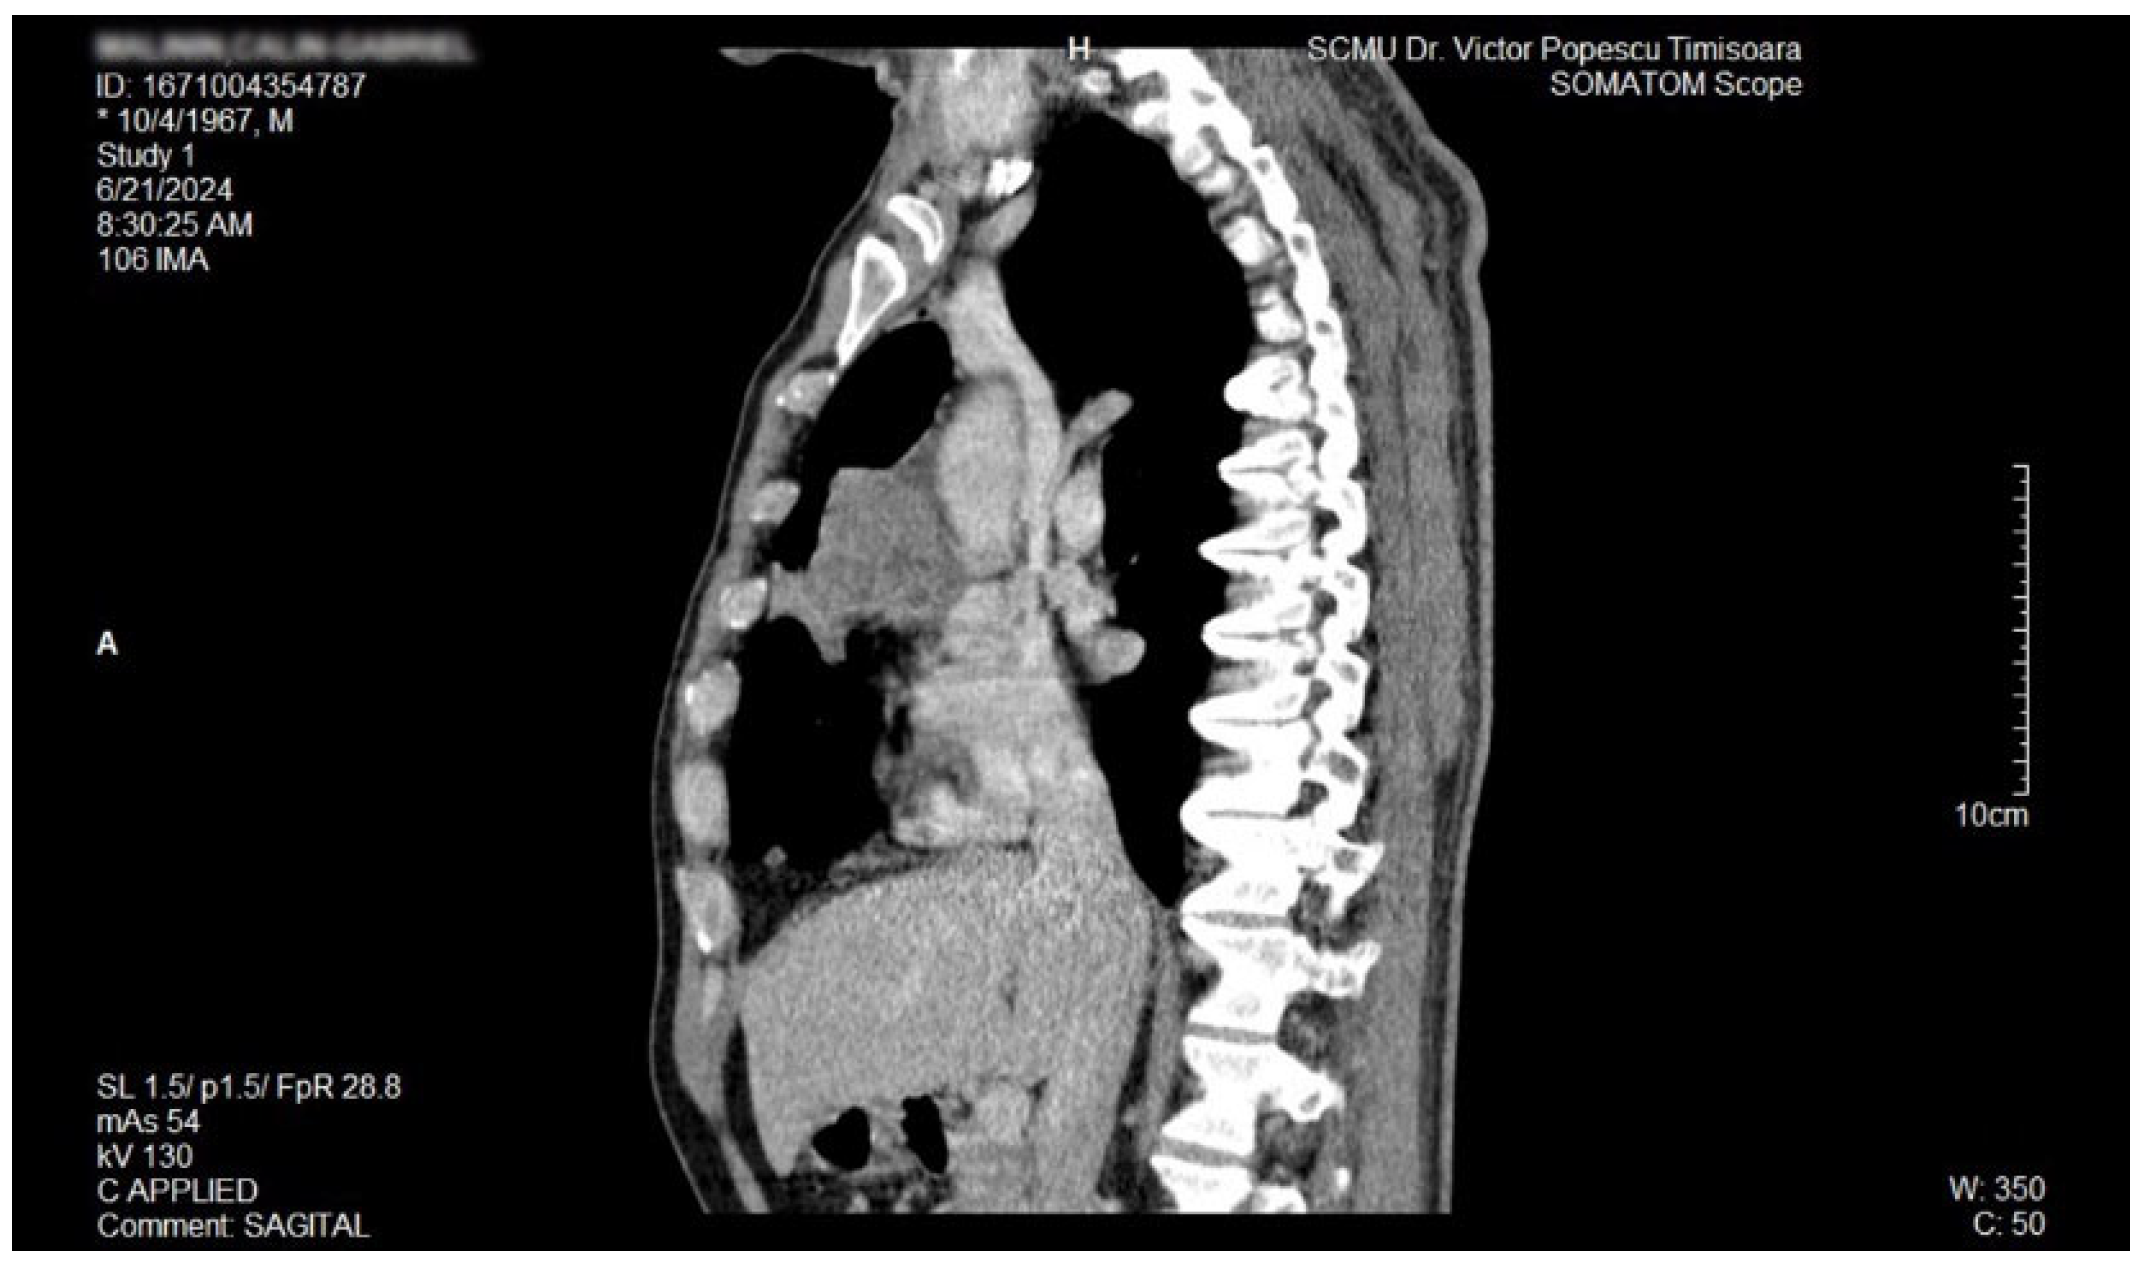

The proposal for H. pylori eradication treatment was initially postponed by the patient. However, the patient received symbiotics in order to alleviate the gut microbiota dysbiosis and also DAO supplementation, aiming at reducing the systemic effects of bacterial histamine overproduction. Further imaging studies were, however, ordered in the context of persistent, treatment-resistant pruritus that lasted for more than 6 weeks and eventually became suspicious for a malignancy. So that thorax and abdomen computed tomography (CT) were recommended and performed soon after, on 21 June 2024. As depicted in Figure 3, Figure 4 and Figure 5, a large right mid-thoracic tumoral formation with mediastinal extension of 7.8 cm/5 cm and a satellite lymph node of 7 mm placed in the anterior aspect of the upper right pulmonary lobe were discovered. The image was considered highly suspicious of lymphoma or pulmonary malignancy.

Figure 5.

Contrast thorax CT: large right midthoracic tumor with mediastinal extension (sagittal view).